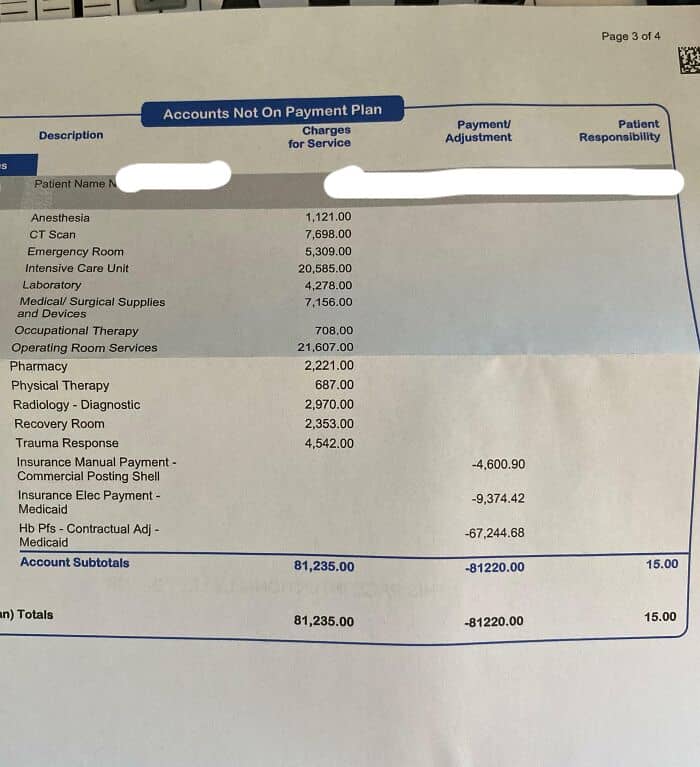

#45 My Kid Was In The Hospital For 3 Days Due To Pneumonia. Thank God We Have Insurance. I Don’t Know How Anyone Can Still Defend U.S. Healthcare